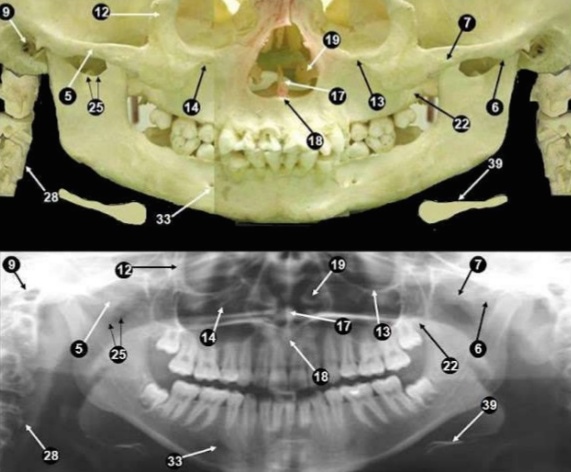

下圖左為顱面的解剖構造,而下圖右則為頭顱骨與”環口”x光下的對應位置

植牙必需確認不會傷及重要的解剖位置。